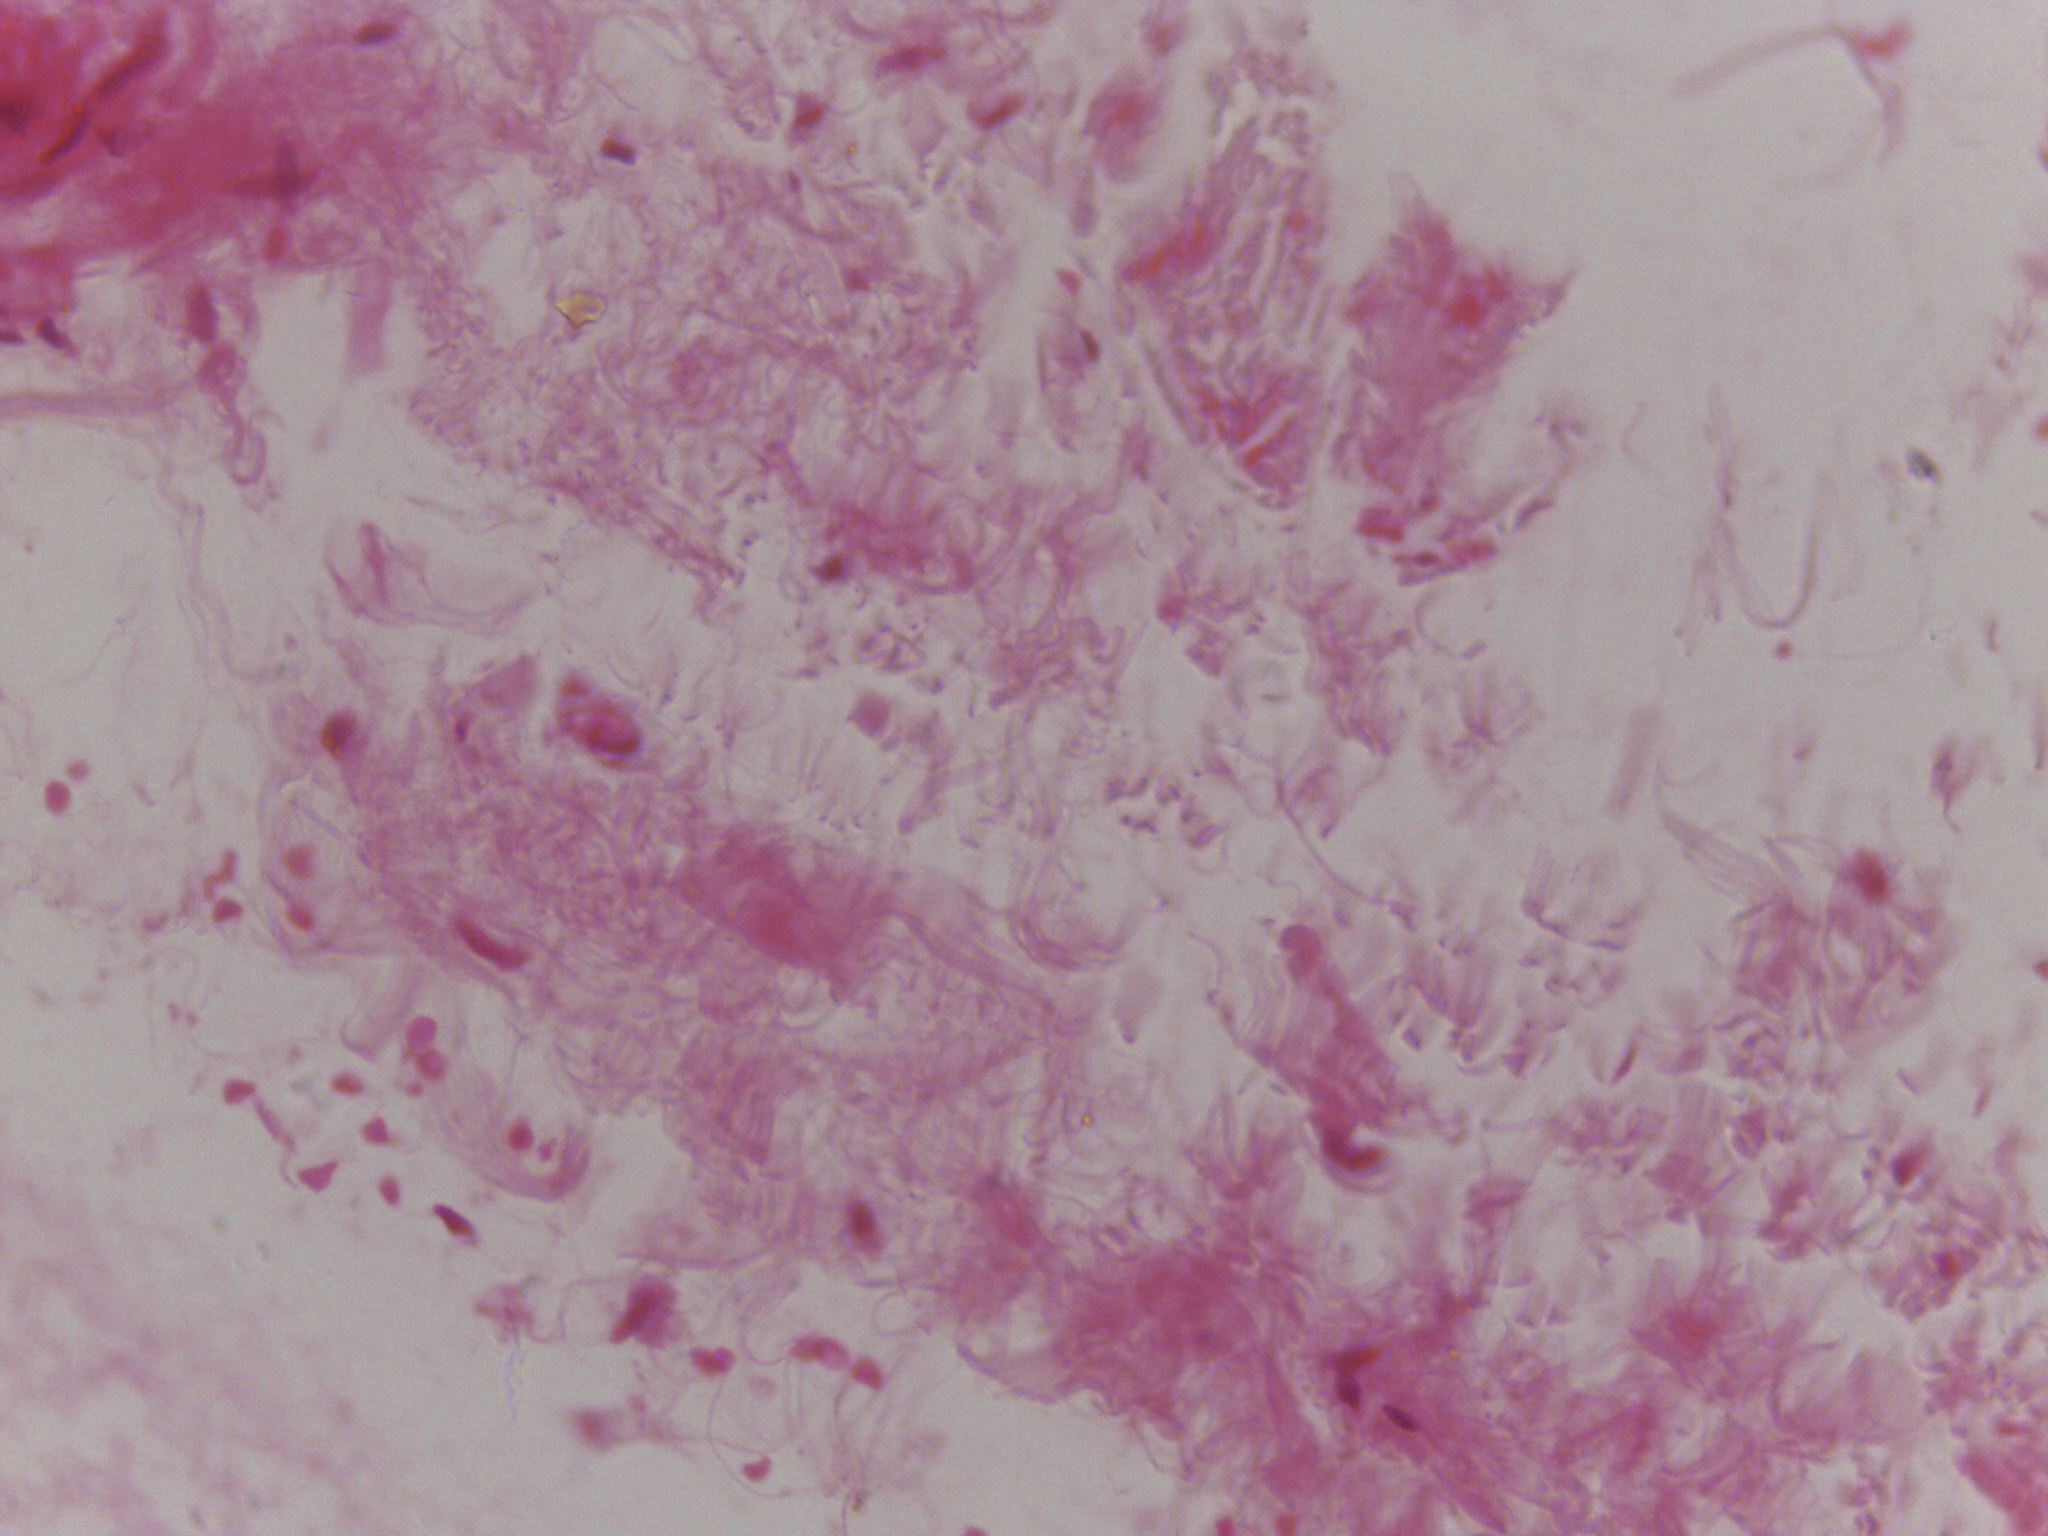

During my four years at university I have found myself being heavily influenced by science and biology, both of humans and plants, but more specifically on the skin and how much visual information can be contained within a single cell. I have been focusing my research on the skin condition vitiligo and the unusual patterns it creates on the body; I’ve always been confused and interested by the random patches so I began an exploration into how skin cells work and how this condition can be triggered. Through this I met some amazing scientists who inspired me through microscope imagery of the skin and lab experiments on the skin. I saw pinks, purples and blues, organic and uncontrolled structures contained within perfect shapes, and patterns hidden to the naked eye.

The imagery that I have gathered of these microscope images and of vitiligo patches has greatly inspired my work, as I have used similar colours and patterns and I have used techniques to try capture the randomness whilst making it controlled and perfected. Below are some of my own imagery that I have taken and some of my own paintings.